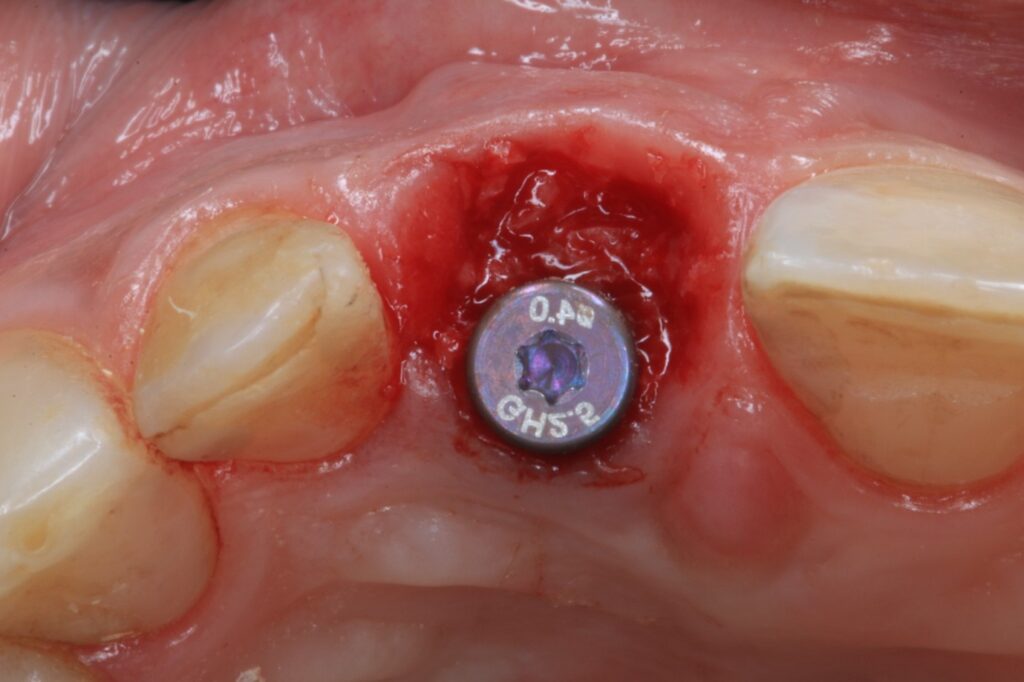

Fig. 2: Implant placed into the fresh extraction socket in the correct 3D position ( Straumann BLX Roxolide SLActive 3.75×12)

- Primary stability: Achieving primary stability is crucial. This may require implants with aggressive thread designs or extended lengths to engage in the apical bone.

- Temporization: In the anterior or premolar region, when primary stability is achieved (insertion torque >35Ncm or implant stability quotient >70), occlusal forces are either absent, minimal, or with shared guidance, and there are no signs of parafunction, immediate loading of the implant with a screw-retained, implant-supported provisional crown can be considered (Lambert et al., 2023). This eliminates the need for a removable provisional, supports soft tissue preservation, and helps prevent apical migration of the soft tissue level (Pitman et al., 2022) (Figures 4, 5). Contraindications for immediate implant placement with immediate loading are mostly related to intraoperative procedural events or a lack of primary stability (Morton et al., 2023; Hamilton et al., 2023).